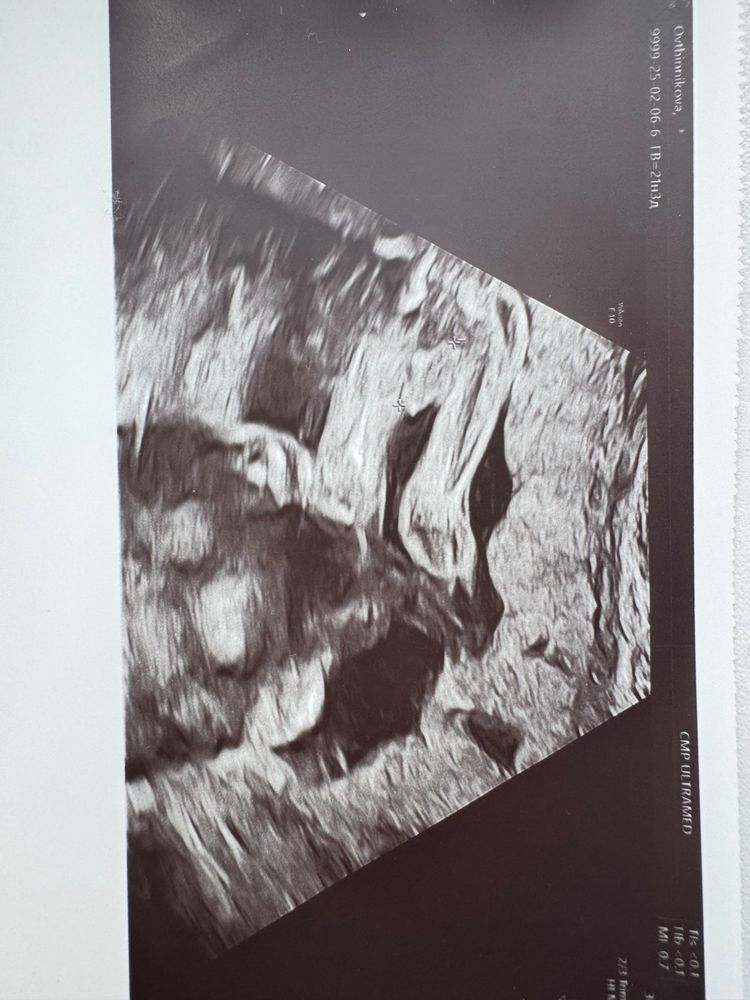

А точно мальчик???

По мне- мальчишка🩵

Мальчик у вас💙

Два яичка и Писюн) вижу, это явно мальчишка

На мой взгляд на фото мальчик. У девочек так не торчит) на пуповину не похоже.

ПоЛ ребёнка Девочки помогите, кто у нас опытный? Мальчик или девочка? Врач предварительно сказала пол, но я не в